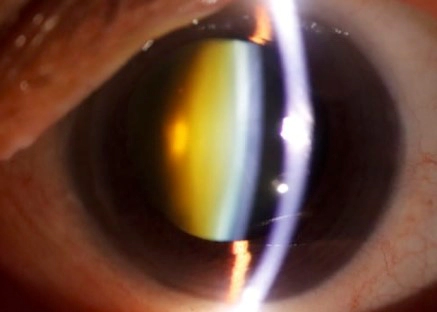

눈의 투명한 수정체가 흐려지면서 발생하는 백내장의 가장 대표적인 초기 증상입니다. 이로 인해 눈물이 자주 나거나 시력이 흐릿해질 수 있습니다. 특히 밝은 빛이나 야간에 더욱 동조되는 증상입니다.

백내장이 발생하면 눈의 수정체가 점차 노랗게 변하며, 이로 인해 색상이 누렇게 보일 수 있습니다. 특히, 파란색과 같은 색상이 덜 선명하게 보일 수 있습니다.